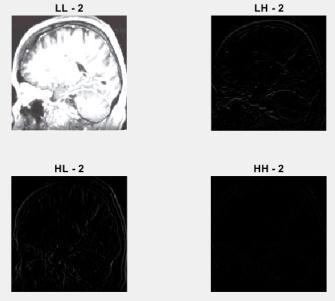

Fig -1:DWTSub-bands

Here, LL band filter in 1-stage DWT decomposition contains a lot of information from the original image. Vertical, horizontal, skew(diagonal) information of the originalimagesisincludedintheLH,HL,andHHbands. LL bandOnlyimagescanreproducetheoriginalimage.Other bandsareignored.

Fig -5(c):applicationofwaveletstoinputimages

The wavelets are applied to both the input image andthewatermarkedimageafterthepre-processingstage, dividingtheimagesintofoursub-bands:LL-1,LH-1,HL-1, HH-1,LL-2,LH-2,HL-2,andHH-2. Here, theLL sub-bands containingthemostinformation.